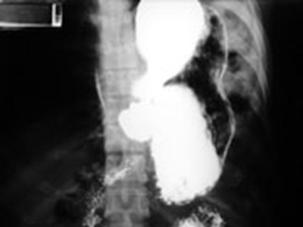

Ruptura de

hemidiafragm stang cu hernierea Ruptura de diafragm

stomacului si splinei Radiografie cu substanta de contrast

Ruptura de diafragm Ruptura de diafragm. Gastrotorax

Ruptura de diafragm. Gastrotorax Imagine CT